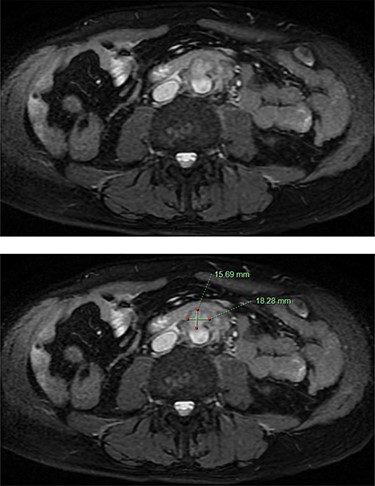

He was afebrile and had generalized abdominal tenderness, worse over the right upper quadrant, without signs of guarding or peritonism. Murphy’s sign was negative. The provisional diagnosis was progression of his PSC, prompting an urgent magnetic resonance cholangiopancreatogram (MRCP). MRCP revealed an infrarenal saccular aneurysm measuring 18 × 16 mm with associated periaortic soft tissue enhancement. There was no evidence of cholangitis (Fig. 1). Blood culture samples and serology for Q fever, mycoplasma and psittacosis were obtained before commencement of IV ceftriaxone and vancomycin.

MRCP demonstrating an abdominal aortic saccular aneurysm measuring ~18 × 16mm with associated periaortic soft tissue enhancement suggestive of a mycotic aneurysm. The study was negative for signs of cholangitis.